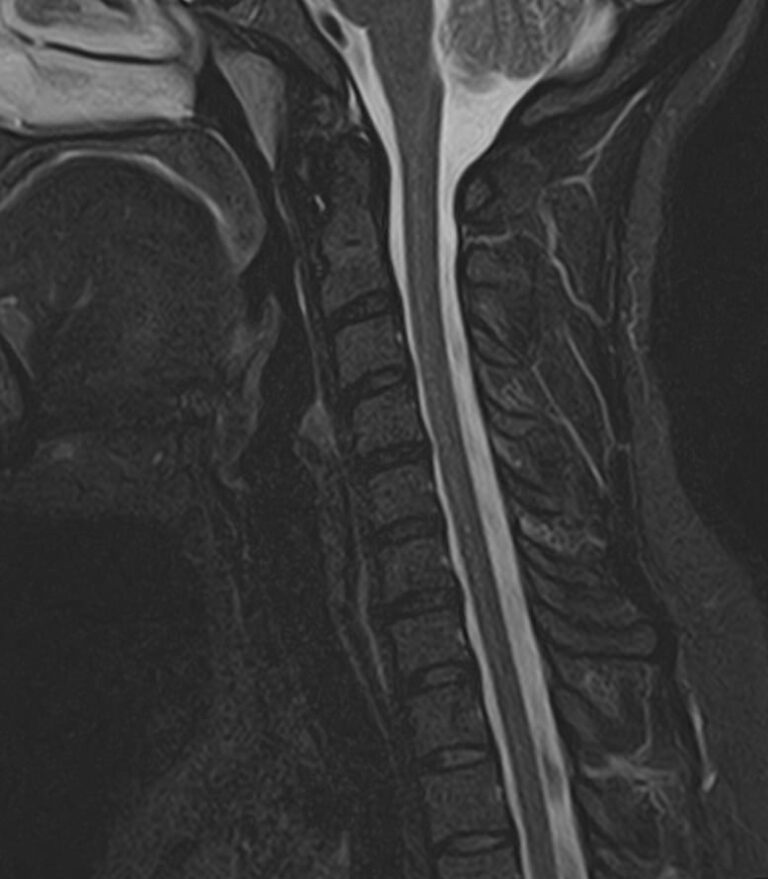

Шейный отдел позвоночника — это самый подвижный сегмент позвоночного столба, который испытывает повышенные нагрузки, подвержен травмам и развитию различных заболеваний. В эту анатомическую область входит 7 верхних позвонков, спинной мозг с отходящими от него нервными корешками.

Кроме того, в области шеи проходят крупные кровеносные сосуды, кровоснабжающие все структуры головного мозга и мягких тканей головы. К ним относятся плечеголовной ствол, сонные и позвоночные артерии, которые далее в полости черепа соединяются между собой в Виллизиев круг. Это анатомическое образование позволяет компенсировать мозговой кровоток при патологических состояниях.

Часто различные нарушения в шейном отделе позвоночника приводят к ухудшению кровоснабжения головного мозга. Опухоли и дегенеративно-дистрофические заболевания шейного отдела позвоночника могут нарушать работу головного мозга. Атеросклеротические бляшки в сосудах шеи могут стать причиной преходящих нарушений мозгового кровообращения (транзиторных ишемических атак) и привести к развитию инсульта. Поэтому важно в комплексе детально визуализировать эти анатомические структуры вместе с оценкой состояния кровеносной системы головы и шеи.

Сканирование проводится на современном высокопольном магнитно-резонансном томографе закрытого типа TOSHIBA VANTAGE TITAN 1,5 Тесла. Магнитно-резонансный томограф производит послойное сканирование исследуемой зоны в разных плоскостях, затем при помощи компьютерных программ преобразует полученные данные в трехмерные изображения. При этом кровеносная система реконструируется как вместе с окружающими тканями, так и отдельно без них.

• остеохондроз, спондилоартроз, спондилез, межпозвонковые грыжи, унковертебральный артроз, сколиоз, усиленный или выпрямленный лордоз как нарушение статической функции позвоночника, травмы, аномалии позвоночника.